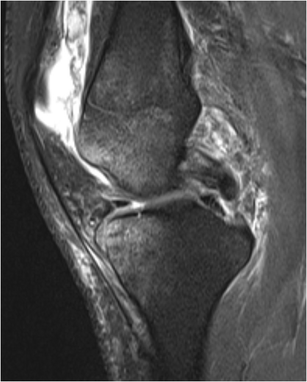

View Bone Contusion Knee PNG. Bone contusion in the knee? A bone contusion, or bone bruise, to your knee is more severe, but it features many of the same symptoms as a knee contusion is a fairly common occurrence.

Posterolateral tibial plateau and mid part of. Is bone contusion treatment knee your major concern? People frequently report bone bruises in the knee, wrist, heel bone, foot, ankle, and hip.